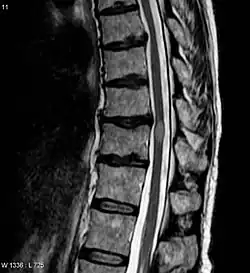

Myelitis has an extensive differential diagnosis. The type of onset (acute versus subacute/chronic) along with associated symptoms such as the presence of pain, constitutional symptoms that encompass fever, malaise, weight loss or a cutaneous rash may help identify the cause of myelitis. In order to establish a diagnosis of myelitis, one has to localize the spinal cord level, and exclude cerebral and neuromuscular diseases. Also a detailed medical history, a careful neurologic examination, and imaging studies using magnetic resonance imaging (MRI) are needed. In respect to the cause of the process, further work-up would help identify the cause and guide treatment. Full spine MRI is warranted, especially with acute onset myelitis, to evaluate for structural lesions that may require surgical intervention, or disseminated disease.[11] Adding gadolinium further increases diagnostic sensitivity. A brain MRI may be needed to identify the extent of central nervous system (CNS) involvement. Lumbar puncture is important for the diagnosis of acute myelitis when a tumoral process, inflammatory or infectious cause are suspected, or the MRI is normal or non-specific. Complementary blood tests are also of value in establishing a firm diagnosis. Rarely, a biopsy of a mass lesion may become necessary when the cause is uncertain. However, in 15–30% of people with subacute or chronic myelitis, a clear cause is never uncovered.[9]